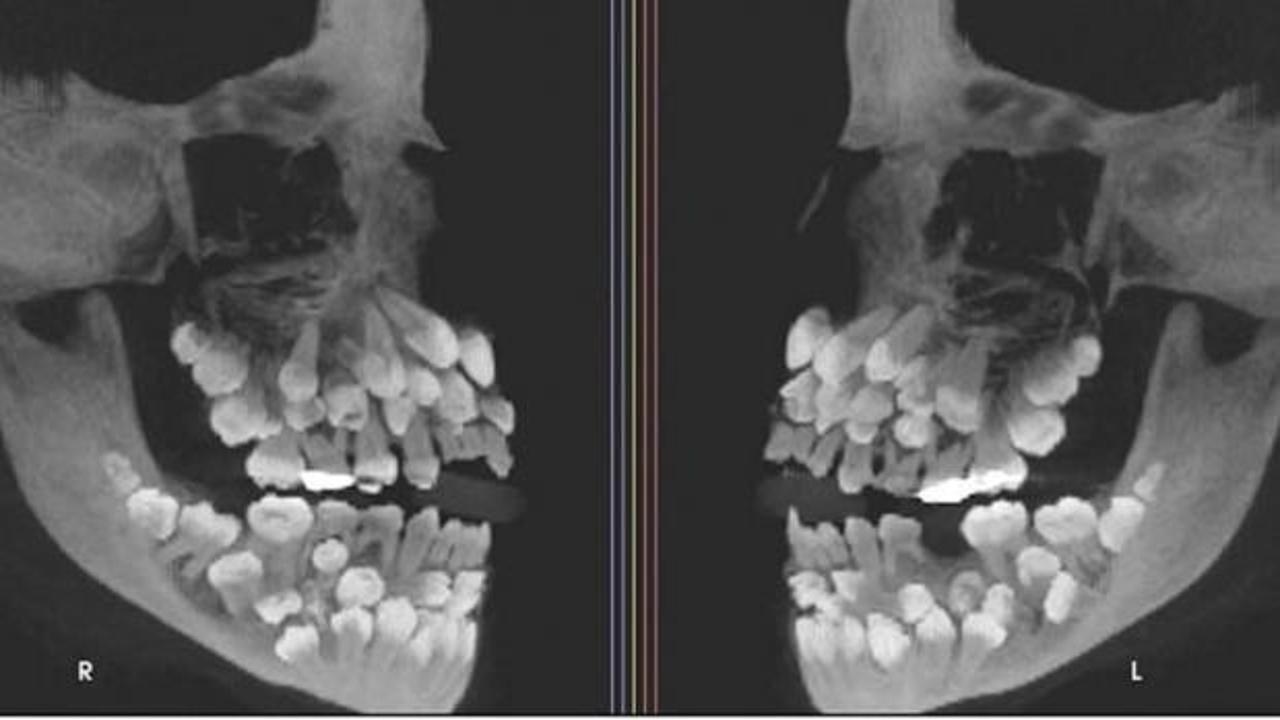

Brezilya'da eşi benzeri görülmemiş bir vaka ile karşılaşıldı. Geçtiğimiz aylarda yapılan bir açıklamaya göre, 11 yaşındaki bir kız çocuğunun ağzında tam 81 diş tespit edildi. Çekilen röntgen filmleri, çocuğun ağzında 18 süt dişi ve 32 kalıcı dişin yanı sıra 31 adet de "süpernümerer" (fazla) diş olduğunu gözler önüne serdi. Yetişkinlerde genel olarak 32 kalıcı diş bulunduğu düşünüldüğünde, otuzdan fazla sayıda süpernümerer dişin bir arada bulunması oldukça nadir bir durum. SADECE BİR TANE DİŞİNİ ÇEKTİRMEK İÇİN HASTANEYE BAŞVURMUŞTU

Başvuruda belirgin bir rahatsızlık belirtisi bulunmadığı ifade edildi. Ancak çekilen röntgen filmleri, çocuğun "çoklu hiperdonti" adı verilen durumu yaşadığını ortaya koydu.

Araştırma ekibi, dişlerin kesin konumunu hassas görüntüleme yöntemleriyle belirledi. Ekip, çoklu hiperdontinin genetik rahatsızlıklarla ilişkili olup olmadığını da titizlikle inceledi.

DİŞLERİ ÇEKMEK İÇİN BİR EKİP KURULDUFazla dişler, diş etlerine derinden gömülü halde bulunabilir ya da normal dişlere benzer biçimler sergileyebilir; bu da kesin bir ayırımı zorlaştırır.

Ayrıca, dişlerin gelişigüzel çekilmesi durumunda çene kemiğinde hasar riski oluştuğundan, tedavi süreci önemli zorluklar barındırıyor.